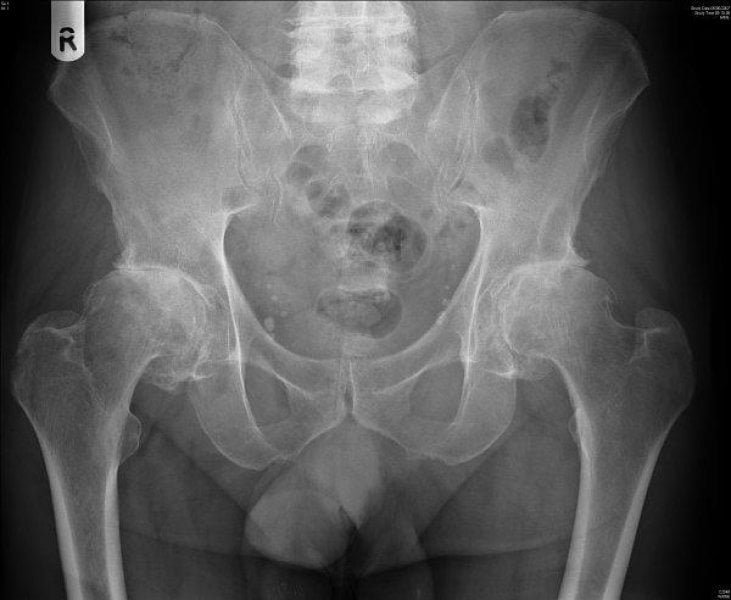

- На снимках отчетливо видна деформация головки сочленения, неровность ее очертаний.

Установить диагноз «коксартроз» помогут следующие исследования:

- УЗИ-диагностика;

- КТ;

- МРТ;

- рентгенография;

- артроскопия (исследование внутрисуставной жидкости);

- анализы крови.